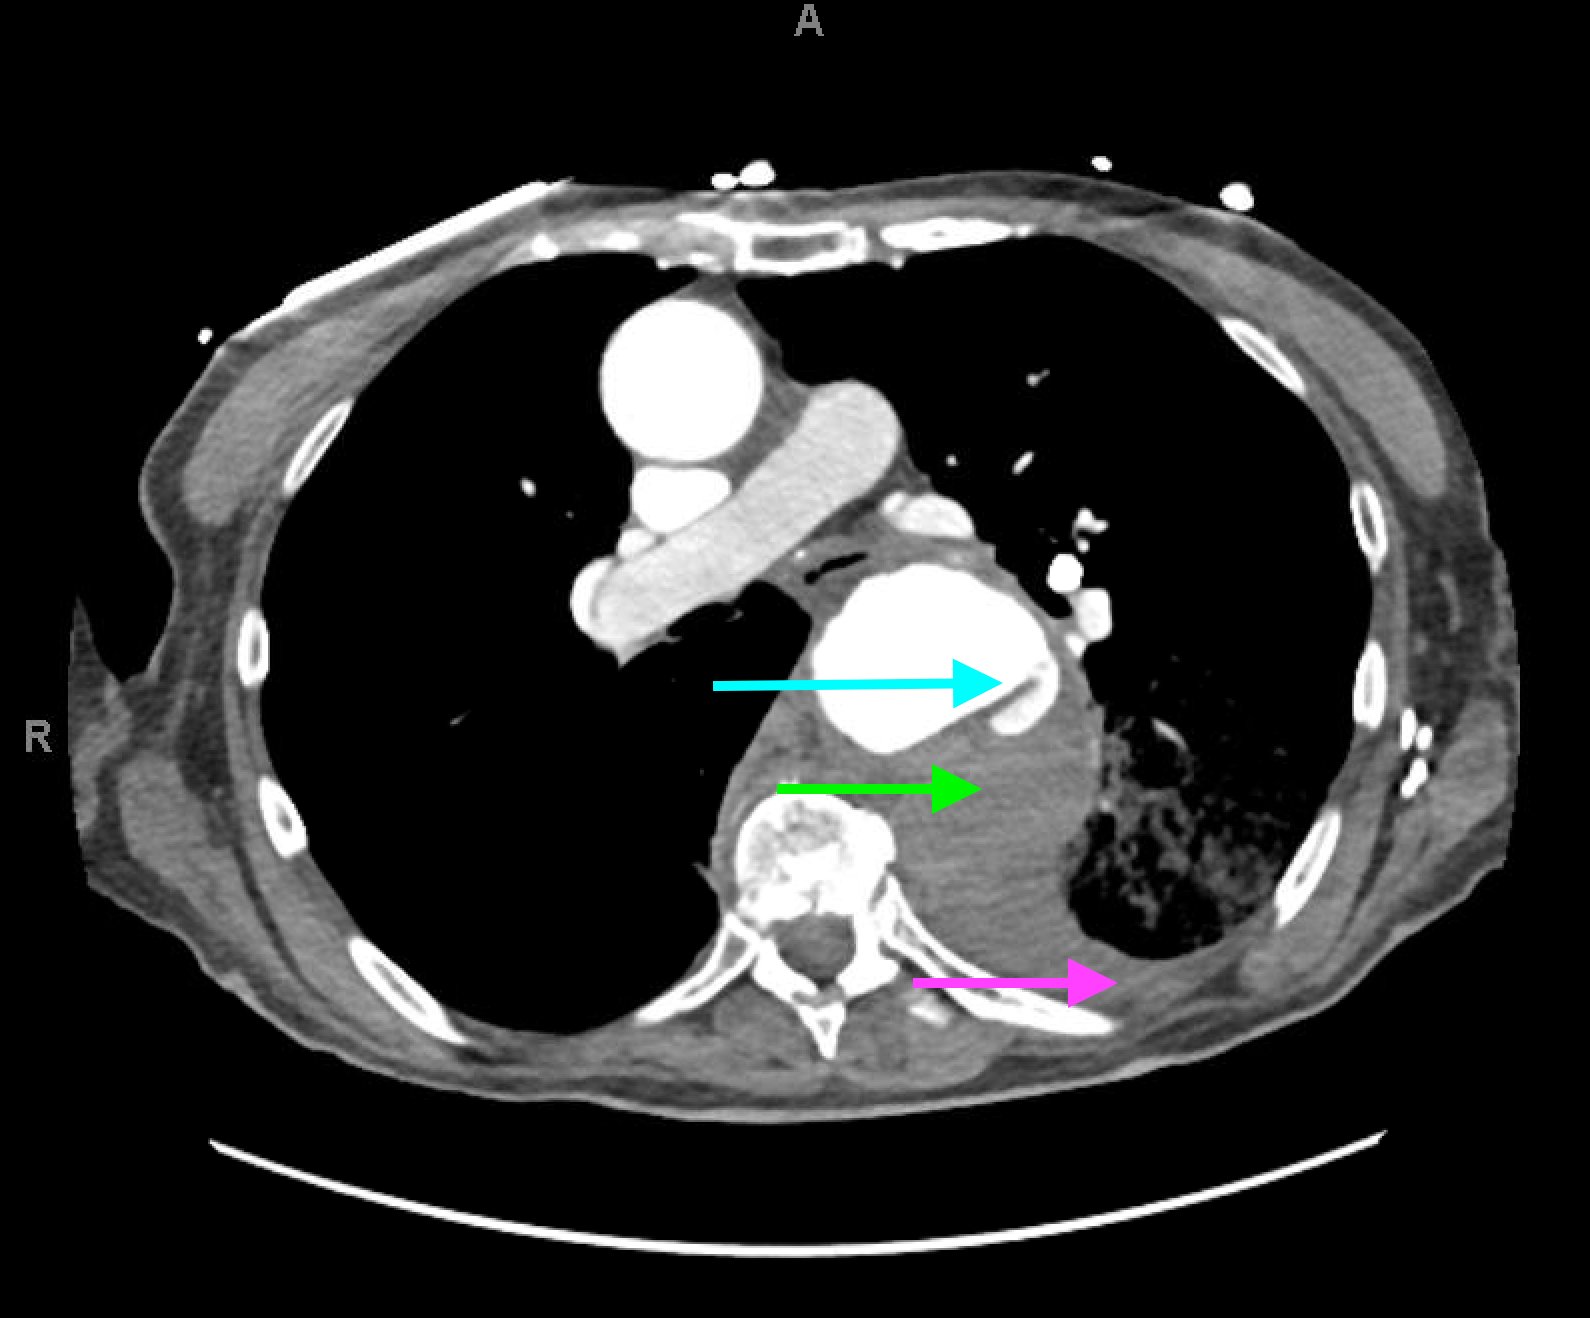

The patient’schest X-ray revealed a prominent mediastinum and opacification in the left middle and lower lung fields. The CT showed an aortic aneurysm extending from the thorax to the abdomen with rupture near T7 (blue arrow). It also showed periaortic hemorrhage with active extravasation (green arrow) likely secondary to a penetrating ulcer and bilateral pulmonary opacities concerning for hemothorax (pink arrow).